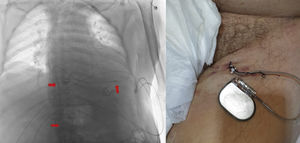

En todos los casos se utilizó un electrocatéter bipolar de 85cm introducido a través de un introductor peel-away de 7-French y avanzado bajo guía fluoroscópica hasta el ventrículo derecho. Umbrales de estimulación menores a 1V fueron considerados aceptables. El electrodo se fijó a la piel con puntos de sutura no reabsorbibles, y se conectó a un generador de pulsos VVI (pool de generadores reutilizables esterilizados), con una frecuencia programada de 60-70latidos por minuto hasta el implante del dispositivo definitivo (fig. 1). Todos los pacientes permanecieron en la unidad hasta el implante definitivo, permitiéndose la sedestación de estos.